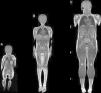

Resonancia magnética de cuerpo completoEl examen de resonancia magnética fue realizado en un equipo 1.5 T Avanto Siemens. Los pacientes fueron posicionados en decúbito supino. Se utilizaron 2 bobinas Body Array y una bobina de extremidades inferiores. El protocolo estándar incluyó localizadores HASTE en planos axial, coronal y sagital, ajustado al tamaño del paciente (fig. 2), con adquisiciones con GRAPPA, 4 bloques secuenciales de imágenes T1w Turbo Spin Eco (FOV de lectura 280-360mm, TR 477ms, TE8,4ms, cortes de 4mm, matriz 512×281, 1.00NEX); bloques secuenciales de 25 cortes de 4mm con secuencia Dixon de 3 puntos, (FOV de lectura 360mm, TR 571ms, TE 11ms, matriz 512×358 interpolada 2.00NEX) en la región masticatoria, cintura escapular, región toracoabdominal, cintura pélvica, muslos, y piernas, con un tiempo total de examen aproximado de 30min (fig. 3).

Las técnicas de resonancia magnética muscular de cuerpo completo han permitido realizar imágenes comparables con la cintigrafía y el PET, sin el inconveniente de la radiación ionizante, y en menor tiempo, lo que ha hecho cada vez más atractivo su uso en pediatría19. La resonancia de cuerpo entero permite un análisis global de la musculatura esquelética y en detalle de la afectación muscular, a través de cortes axiales contiguos que se extienden desde la cabeza hasta los pies. La graduación del grado de infiltración grasa se ha realizado hasta ahora según métodos semicuantitativos que valoran, a través de una escala visual, el grado de infiltración grasa de los diversos músculos en secuencias ponderadas en T120.